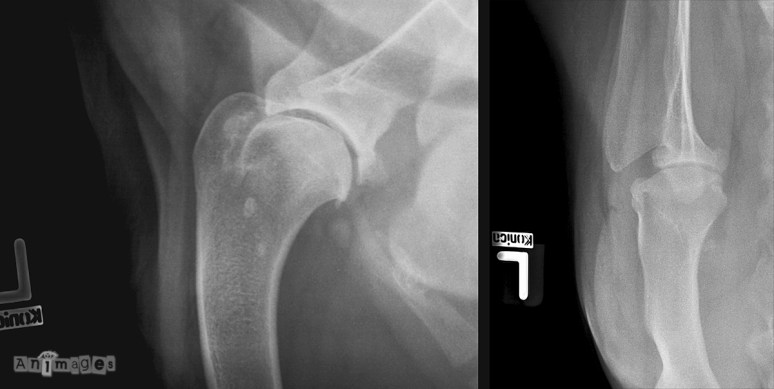

Signalement: Rottweiler, mâle intact de 6 ans.

Histoire clinique: Boiterie chronique au membre thoracique gauche. Douleur à l’extension et rotation de l’épaule.